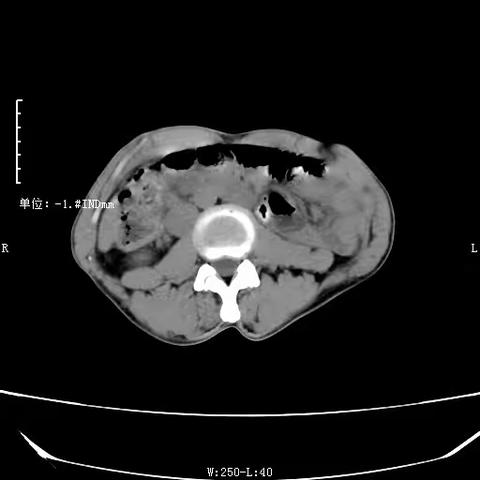

异位肾病例分享

2022-10-12 505阅读